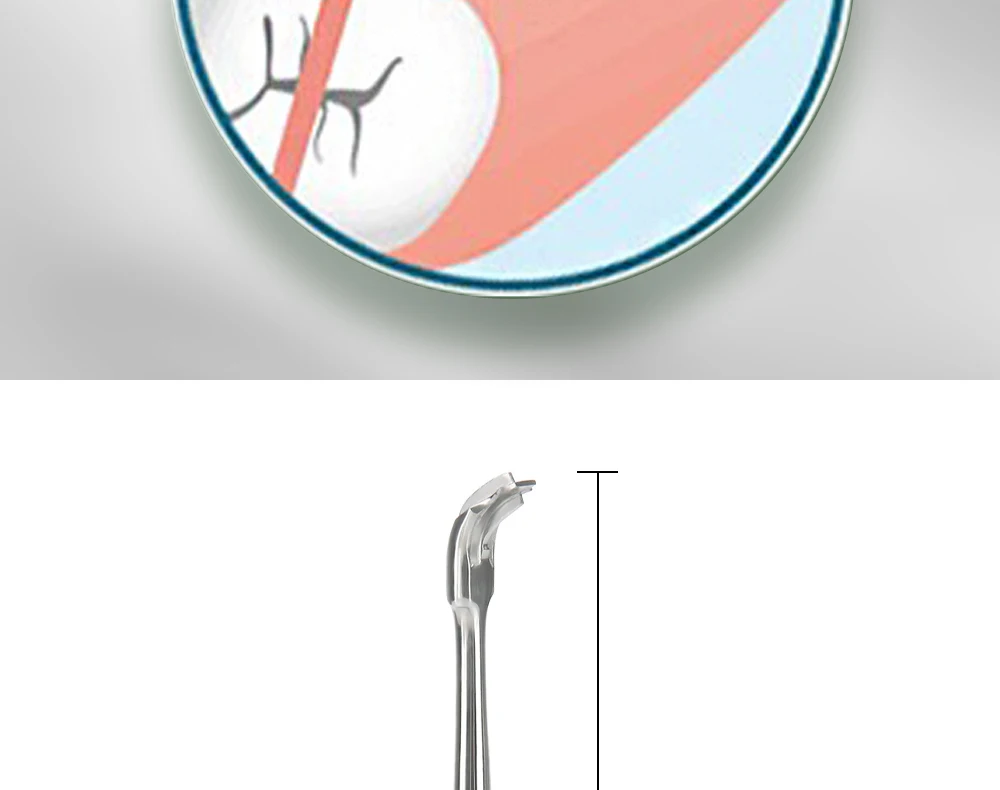

- Стоматологічне обладнання та інструментарій

- Базовий стоматологічний інструмент та обладнання

- Стоматологічні роторасширители

- Стоматологічне обладнання та інструментарій

- Базовий стоматологічний інструмент та обладнання

- Стоматологічні роторасширители